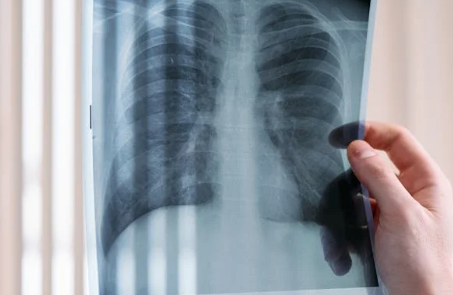

肺大泡(肺大疱)虽看似局部问题,但其潜在影响却可能蔓延至整个呼吸系统乃至全身,需引起足够重视。

随着肺大泡体积增大或数量增多,周围健康的肺组织会持续受到压迫,导致肺泡无法充分进行气体交换。这不仅会引起咳嗽、胸闷、活动耐力下降等症状,还可能进一步削弱肺功能,甚至诱发或加重慢性支气管炎、肺气肿、哮喘等疾病。在进展较快的病例中,还可能逐渐演变为慢性阻塞性肺疾病或呼吸衰竭。

肺大泡破裂是自发性气胸最常见的原因。一旦破裂,气体进入胸膜腔,肺部受压塌陷,患者可能突发剧烈胸痛与呼吸困难,属于呼吸科急症,需立即就医,否则可能危及生命。